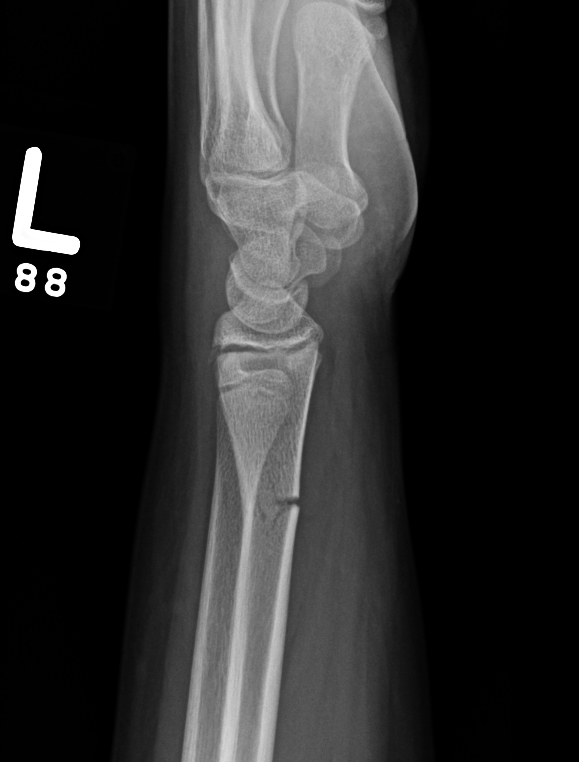

colles fracture

smiths/ reverse colles fracture